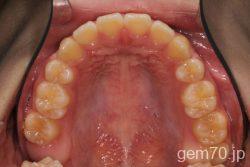

症状:開咬装置:セラミックブラケット | 抜歯世代:10代 | 高校生

主訴)前歯がかみ合わない

診断)開咬

年齢)18歳

使用装置)マルチブラケット装置

治療方法)抜歯 4|4/4|4

治療期間) 2年4ヵ月 通院回数 27回